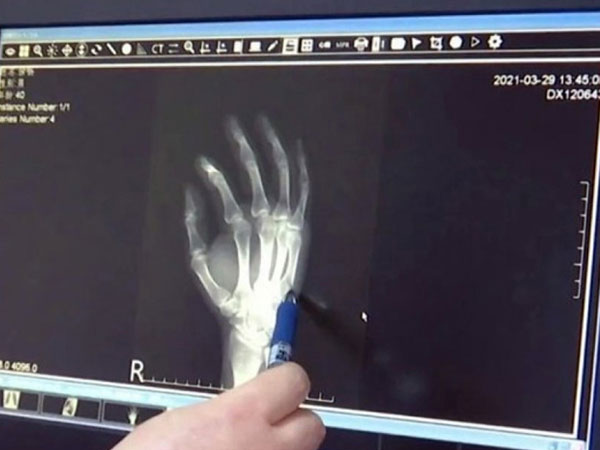

Trang 1Ông bố gãy tay vì đập bàn khi dạy con học

Bực tức vì con không chịu làm bài, người cha họ Xu đập tay xuống bàn khiến lòng bàn tay bầm tím, sưng tấy và đau nhức kéo dài.